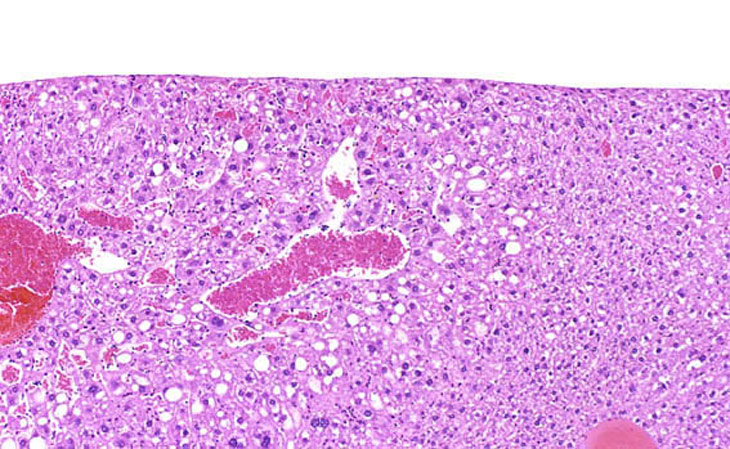

These examples represent low magnification views of angiectasis.